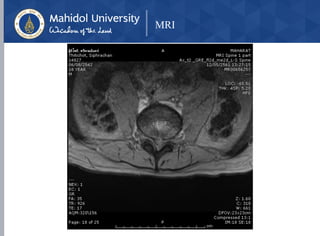

MRI

Herniated Nucleus Pulposus at L3-L4, L4-L5

With cauda equina syndrome

• MRI

• Modality of choice